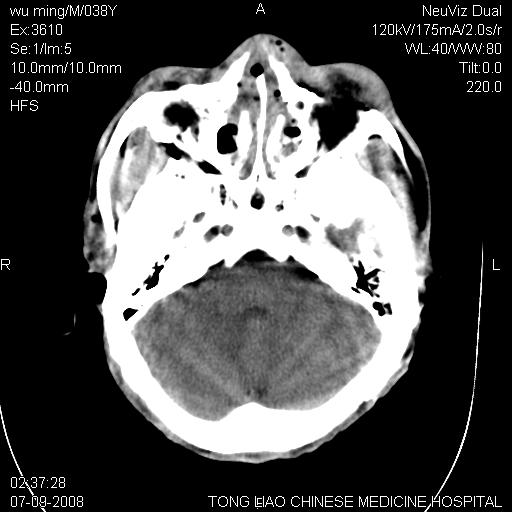

标题: CT14544:患者5楼坠下15分钟后CT扫描,2小时后死亡,请战友指 [打印本页]

标题: CT14544:患者5楼坠下15分钟后CT扫描,2小时后死亡,请战友指

颅底多发骨折。

颅底多发骨折.

颅底多发骨折.上颌骨多发骨折

右侧眼眶,上颌骨,鼻骨、上颌窦等很多

考虑:面骨、颅底骨多发骨折,颅内高压(脑肿胀)。

面骨、颅底骨多发骨折,右侧硬膜下小血肿,弥漫轴索损伤,死亡原因可能是多种因素致。

1)颅底骨及颌面骨多发性骨折。2)副鼻窦及双侧鼻腔积血。

颅底骨折,窦腔内积血。考虑死亡原因为脑水肿压迫脑干或因大量失血死亡。

前颅窝颅底骨折,死的原因应该从头部来看不用说就是重度颅脑损伤。

颅底、上颌骨,双侧颧骨多发骨折。死因或许与此无关,是否有腹部脏器损伤有关

考虑:面骨、颅底骨多发骨折。从五楼摔下还伤着头了,不死才怪;估计有弥漫性轴索损伤。